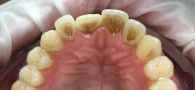

Пациентке нашей клиники требовалось устранить налёт на поверхности зубов. Врач-гигиенист Саражинская Валерия Владимировна провела осмотр полости рта и предложила провести процедуру профессиональной чистки зубов с помощью эффективных методик.

После процедуры пациентка осталась довольна результатом и внешним видом своих зубов. Проблема была успешно решена.

Всего за 1 визит Валерия Владимировна провела необходимые манипуляции и зубы пациентки стали гладкими, белыми и блестящими!

Процедура профессиональной гигиены включала следующие этапы:

• Осмотр и оценка состояния полости рта;

• Удаление зубного камня с помощью ультразвукового скайлера

• Устранение мягких зубных отложений аппаратом Air Flow;

• Полировка зубов специальной пастой и щётками.